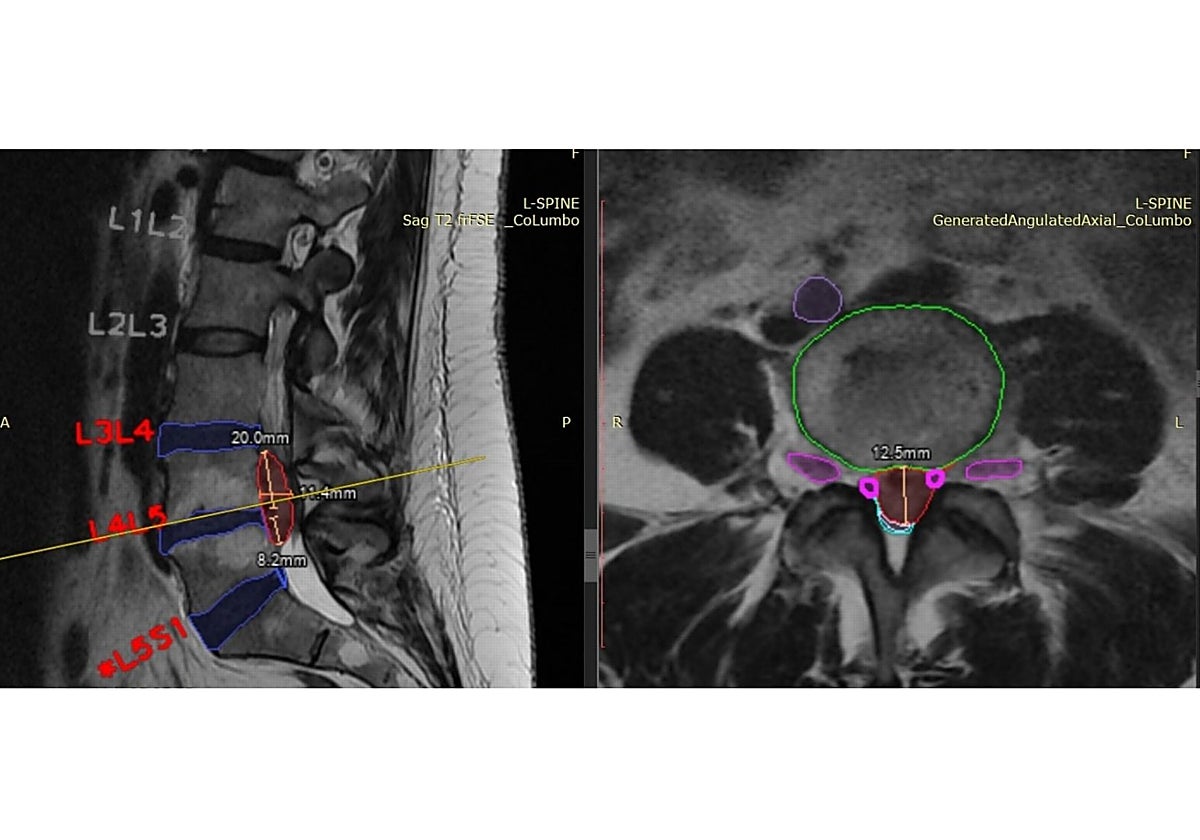

Pero, a pesar de la capacidad ya contrastada de la IA para interpretar imágenes avanzadas (como ecografías o radiografías), analizar y cruzar grandes cantidades de datos u ofrecer una monitorización constante del estado de salud, quedan retos pendientes. El estudio pone también de manifiesto la necesidad de llevar estos avances a la práctica clínica, para lo que se requiere de una infraestructura a día de hoy inexistente. Además, los expertos ponen el foco en reforzar la transmisión de conocimientos entre la academia y la empresa, así como los riesgos que supone para la protección de los datos de los clientes, necesarios para alimentar la base de datos que la IA utiliza para todas sus aplicaciones.

El informe incluye mesas de debate en las que participaron decenas de expertos y entre los que se trataron estos asuntos, así como algunos de los casos prácticos llevados a cabo en la Comunidad. Entre ellos, se expuso el uso de la IA en algoritmos de cribado en retinopatía diabética y mamografías, así como en el soporte en la toma de decisiones clínicas o a la hora de predecir e identificar complicaciones futuras de los pacientes y ofrecer tratamientos personalizados. El principio de lo que podría suponer una revolución para la medicina.